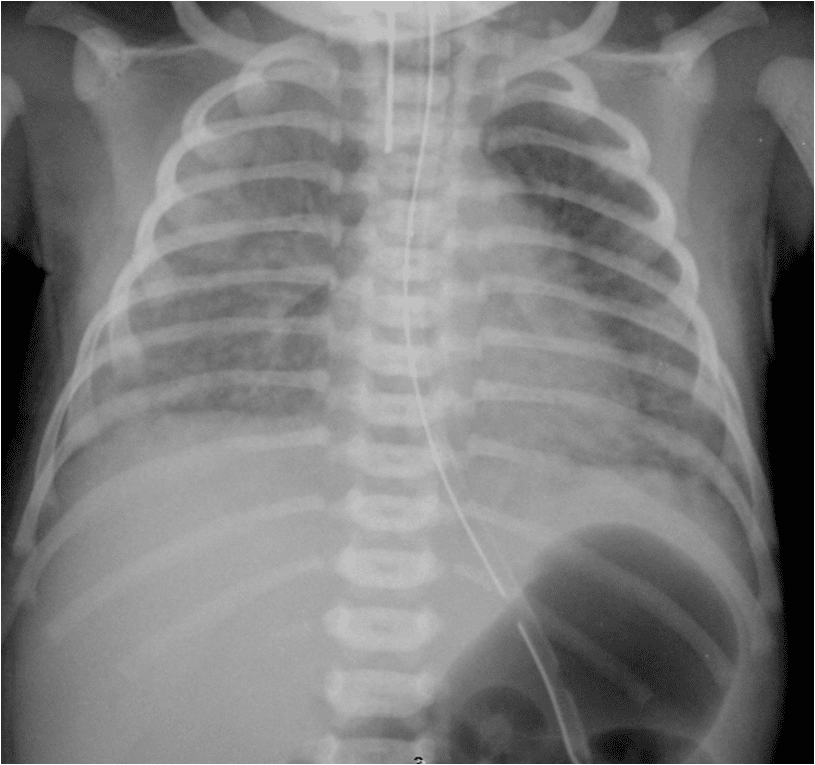

From radiologyspot.blogspot.com

RADIOLOGY IMAGE SPOTTERS Meconium aspiration Meconium Aspiration Definition Medical Meconium aspiration is when a newborn breathes in a mixture of meconium and amniotic fluid. Meconium aspiration syndrome (mas) is the neonatal respiratory distress that occurs in a newborn in the. Meconium aspiration syndrome (mas) is defined as respiratory distress in the newborn due to the presence of meconium in. Amniotic fluid is the liquid that surrounds the. Meconium aspiration. Meconium Aspiration Definition Medical.